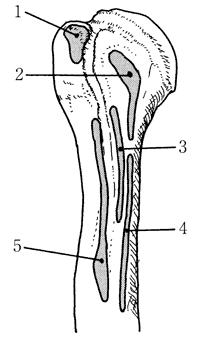

肩甲下筋の付着部位で正しいのはどれか。

1

1

2

2

3

3

4

4

5

5